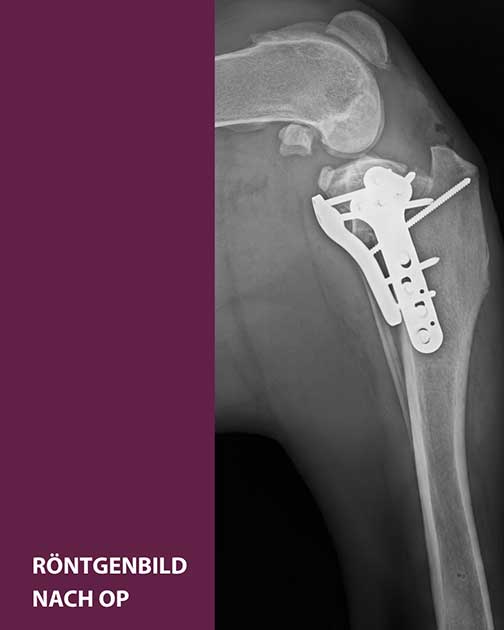

TPLO bei einer Riesenrasse: Die Röntgenbilder zeigen den Kreuzbandriss von Dogge Apollo – einmal vor, einmal nach der Operation.

Klinikleiter Dr. Zahn, der die Operation selbst durchführte, entschied sich für die sogenannte TPLO – ein bewährtes Verfahren, bei dem der Schienbeinkopf durchtrennt, in seiner Neigung verändert und mit einer speziellen Metallplatte fixiert wird. Ziel ist es, die Biomechanik des Kniegelenks so zu verändern, dass es auch ohne funktionierendes Kreuzband stabil bleibt.

In Apollos Fall wurde der Schienbeinkopf um rund 30 Grad rotiert. Während bei normal gewichtigen Hunden eine Knochenplatte ausreicht, kamen bei Apollo zwei Platten zum Einsatz – für maximale Stabilität der Riesenrasse.

Bereits zwei Tage nach der Operation belastete Apollo sein Bein wieder. Bei der Nachkontrolle sechs Wochen später zeigte sich ein ausgezeichneter Heilungsverlauf: Der Knochenspalt war nahezu vollständig verheilt, das Gelenk stabil. Apollo durfte sein Bein zunehmend belasten – und war, laut seiner Halterin, kaum zu bremsen. Auch in der laufenden Physiotherapie macht er gut mit und weiterhin beste Fortschritte.